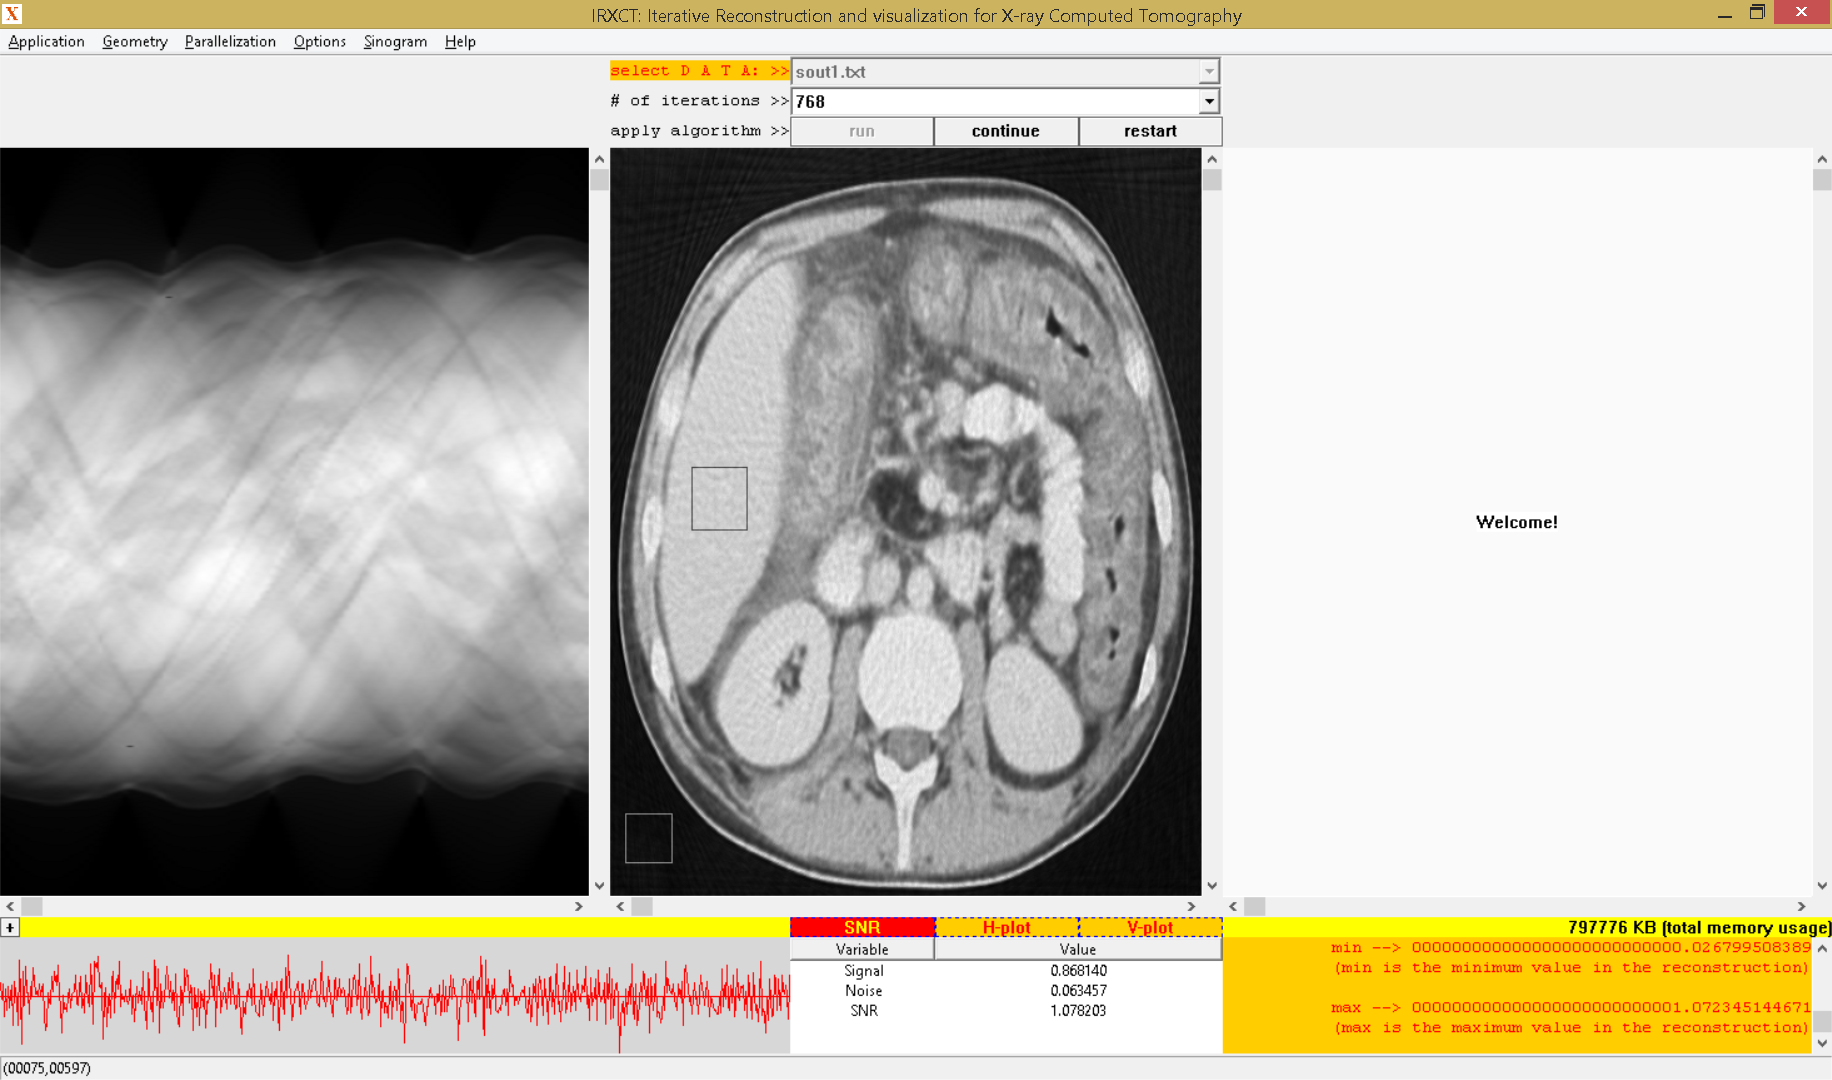

Refer to caption

Figure 4: Situation after running all 768 iterations

With the sinogram and the number of iterations chosen, we press the ”run” button so that calculation of the system matrix (using area integrals) and then the reconstruction start. During the calculation of the system matrix the yellow static control right above the report window shows in real-time the current memory usage of the application. Once the system matrix is calculated, the iterations start and after each iteration the reconstruction window shows the reconstruction updated and the convergence window shows the plot of the convergence. For example, Figure 3 shows the situation after iteration 58. In Figure 4 it is shown the reconstruction after all 768 iterations are completed. After all 768 iterations are completed, the report window shows a report consisting of four indicators:

1. 1.

”time 1” is the time (double type) taken to calculate the system matrix (in this example, it is 38.006 seconds)

2. 2.

”time 2” is the time (double type) taken to run the 768 iterations (in this example, it is 315.007 seconds)

3. 3.

”min” is the minimum value (double type) in the reconstruction (in this example, it is approximately 0.026)

4. 4.

”max” is the maximum value (double type) in the reconstruction (in this example, it is approximately 1.072)